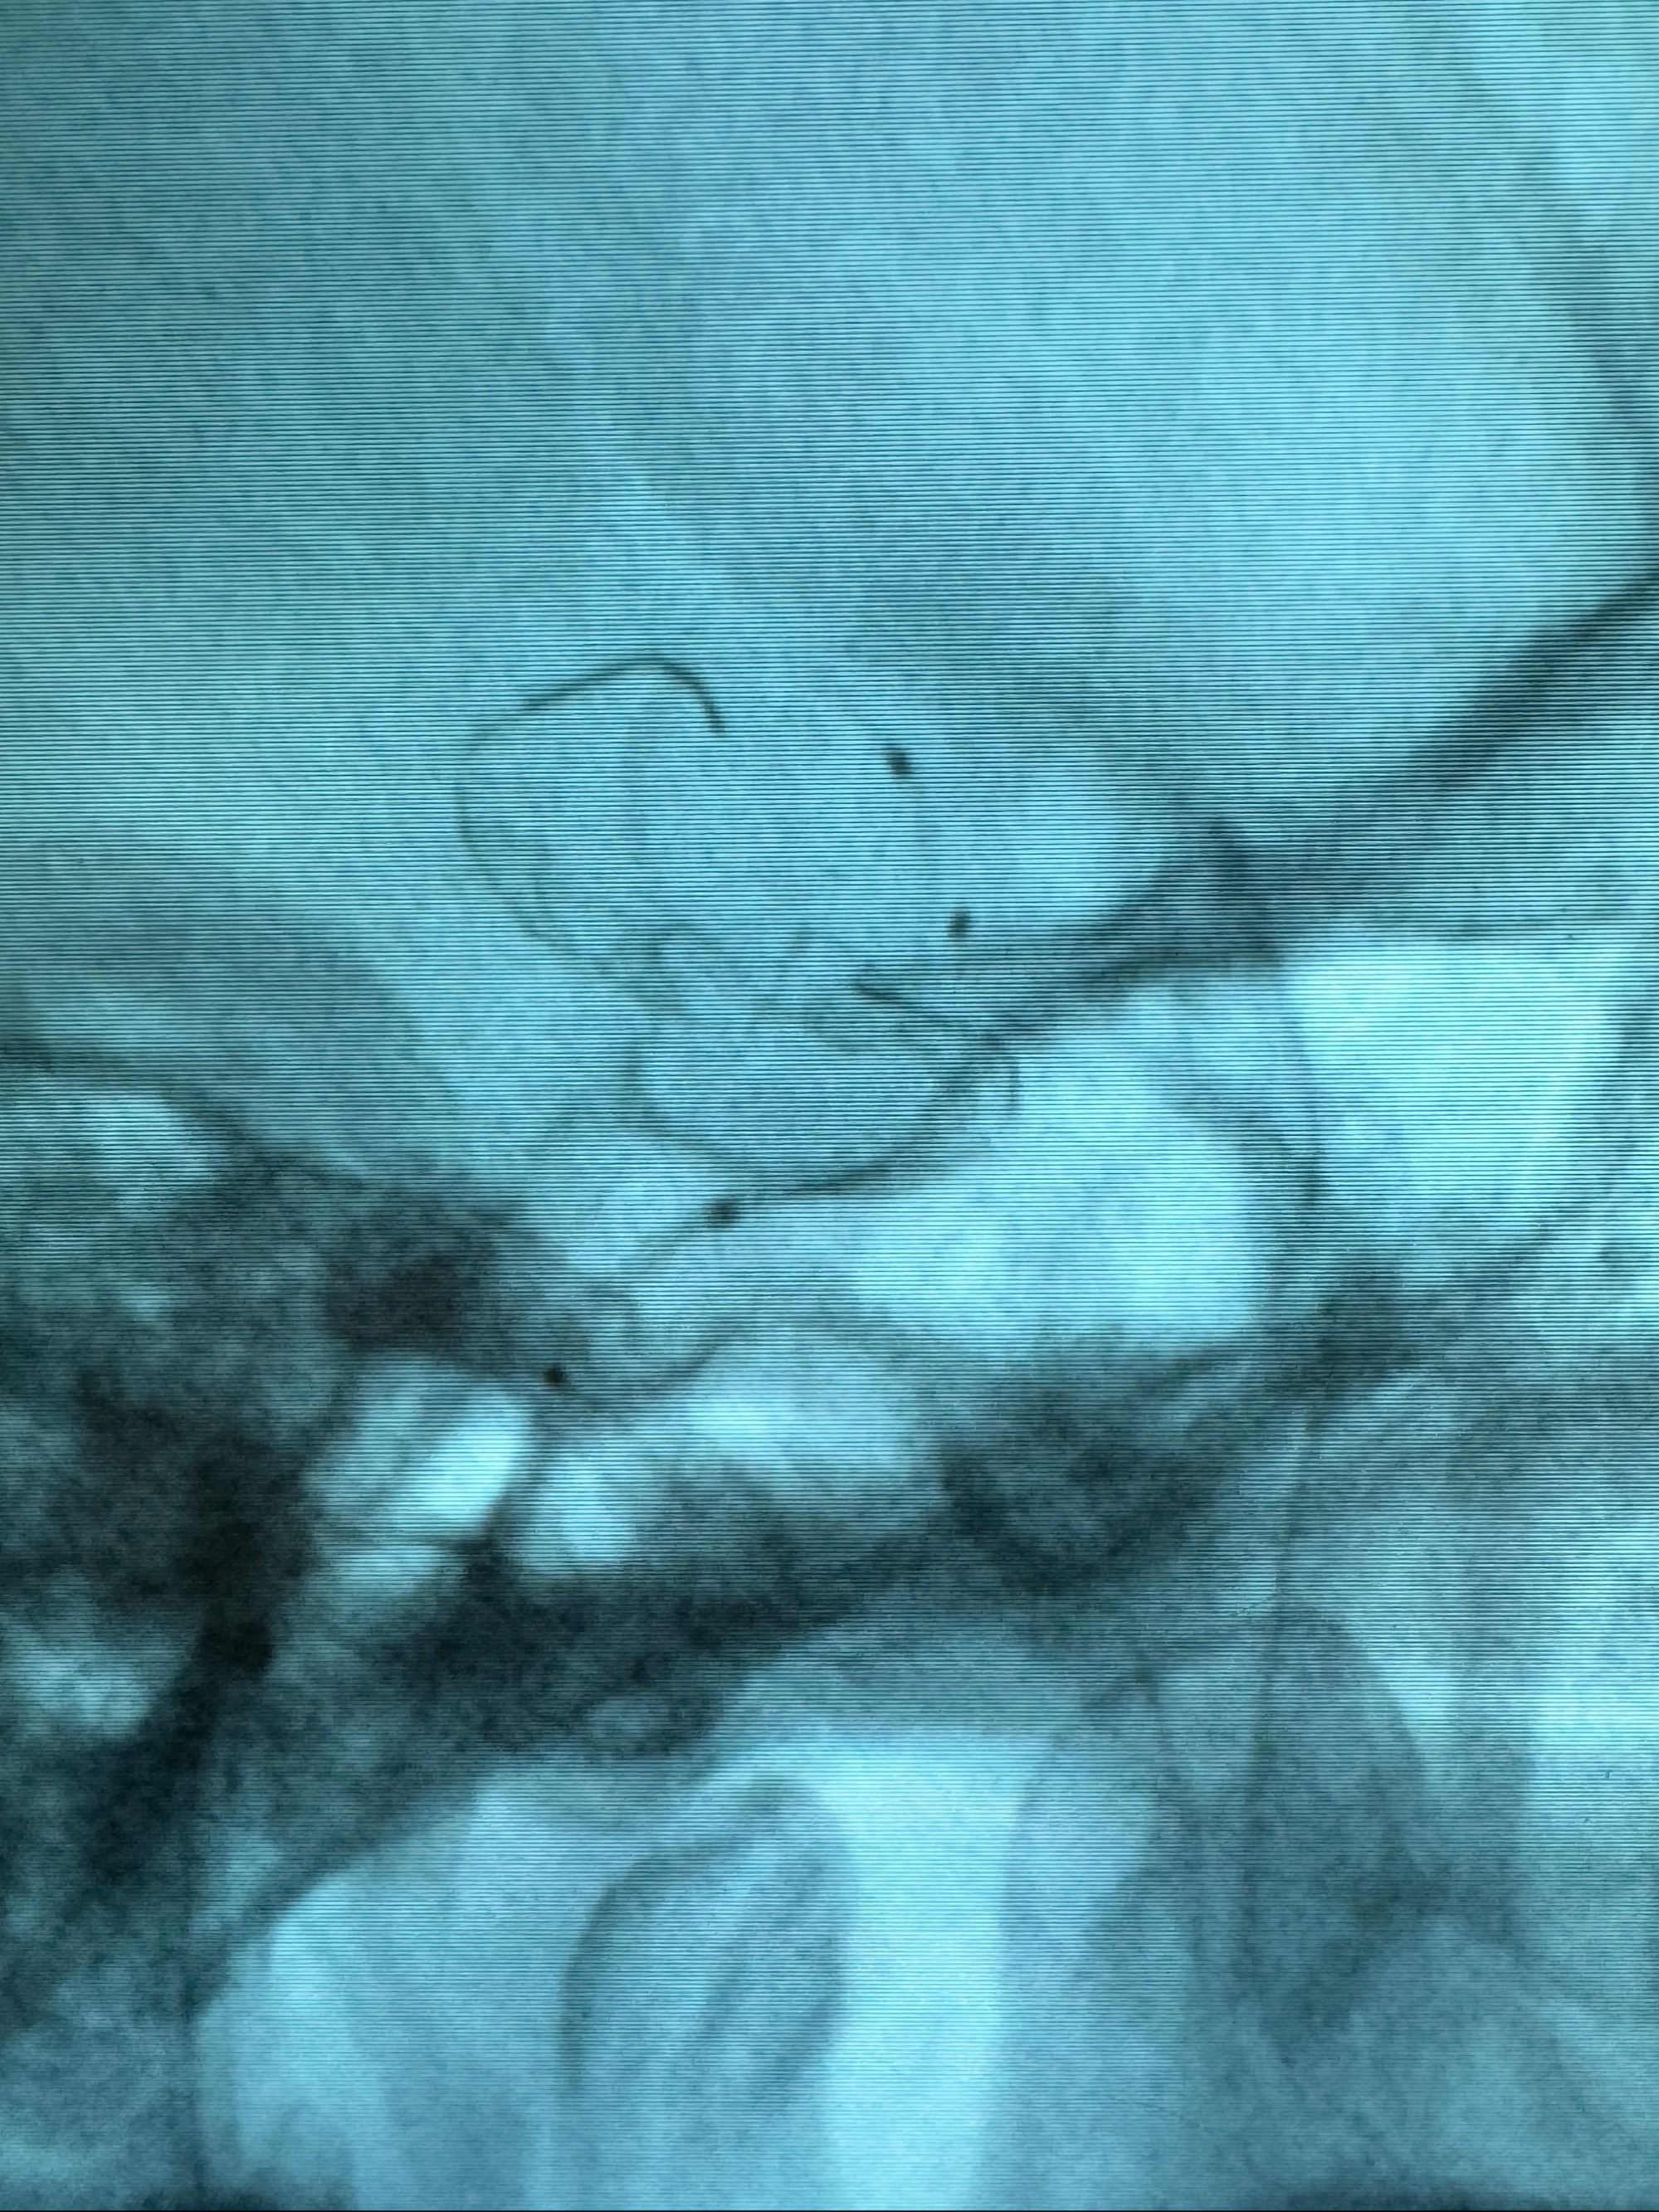

逐帧图像展示歪着脖子释放支架,旁边吩咐助手手机摄影、拍照留像(透视机不能留影像)

接下的视频为释放支架的过程及试图确认支架与血管的关系

最后再看看颅内血管是否有异常

看动脉瘤内造影剂滞留,未见明确射流,遂撤出预留的栓塞微导管,快速结束手术,经导引导管灌注替罗非班250ug。